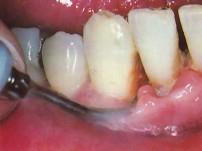

使用超声波洁牙机时,工作头应与牙面成 ( )

- A.20度角左右

- B.10度角左右

- C.80度角左右

- D.25度角左右

- E.15度角左右

E